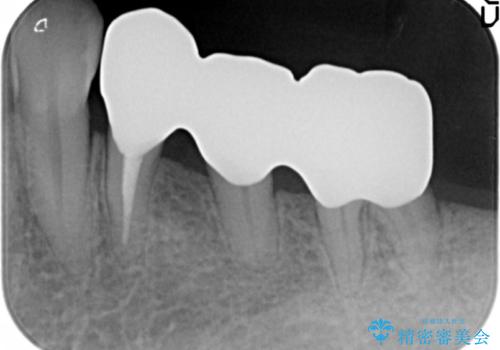

再生療法と骨外科処置により、歯周ポケットは全周2mm以下となりました。

根本的な歯周病の治療を行うことで不安がなくなり、患者様に喜んで頂けました。

また、奥歯の動揺がなくなりしっかりと咬むことができ、審美的・機能的にもご満足頂けました。

被せ物の種類:オールセラミッククラウン ベレッツァ